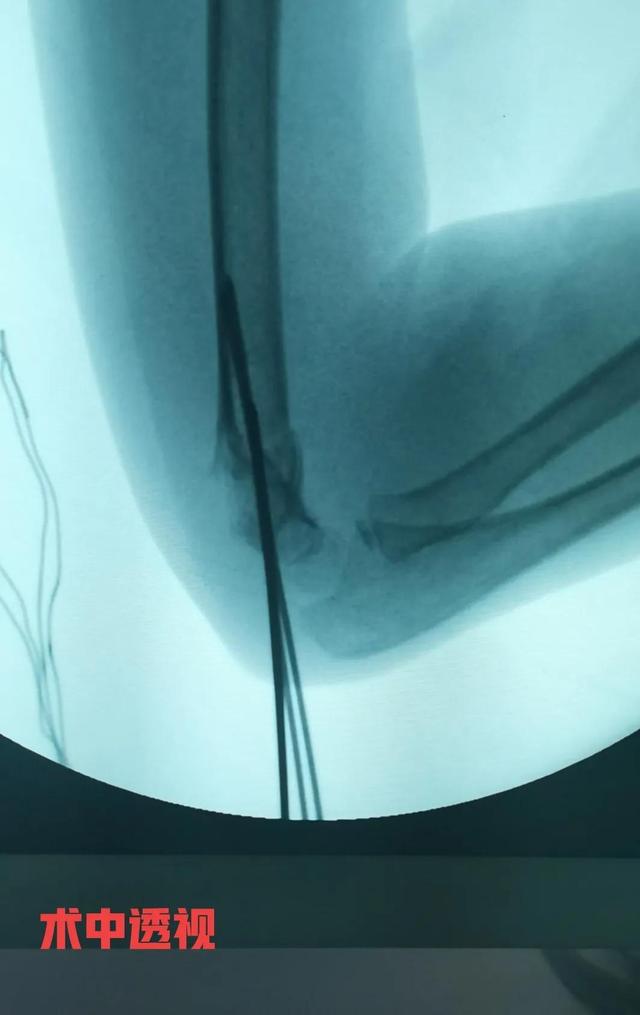

病例 女性,7岁,跌伤,右肱骨髁上骨折